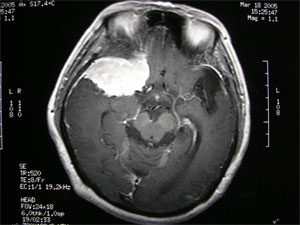

3.CT掃描 可見到以蝶骨嵴為中心的球形生長的腫瘤,邊界清楚經對比增強後腫瘤影明顯增強,如腫瘤壓迫側裂靜脈腦水腫較顯著。蝶骨嵴腦膜瘤CT掃描常有重要發現:①眼眶外壁或蝶骨嵴骨增生肥厚,瀰漫隆起或不規則增生,邊界不清楚偶可見局部骨破壞;②眼眶側或顱內有軟組織塊影,腫物常呈扁平形或不規則形,晚期腫瘤可能體積較大;③其他徵象包括:腦膜瘤尾征。

4.MRI MRI對診斷本病是有意義的。MRI可以顯示腫瘤與蝶骨翼和眼眶的關係,骨質破壞情況等。尤其是對內側型的蝶骨嵴腦膜瘤,MRI還可以提供腫瘤與頸內動脈的關係,有時腫瘤將頸內動脈包裹在內,或腫瘤附著在海綿竇上這些情況對手術切除腫瘤均有重要的參考價值。增強後的MRI圖像更清晰。

蝶骨嵴腦膜瘤在T1WI和T2WI上呈低信號或中信號增強明顯和CT相比,MRI對於體積較小的腫瘤顯示較好。顱內惡性腦膜瘤可侵及眶內、顱內,呈多發腫瘤。